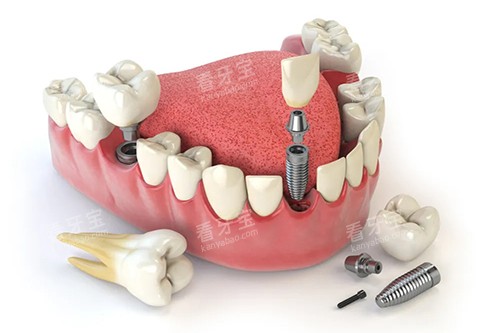

在治疗设备方面,登特口腔医院拥有新型的种植牙设备和技术。

种植牙是目前修复缺失牙的比较佳方式之一,医院引进的种植牙系统具有稳定性高、成功概率高、舒适度好等优点。

医生们利用新型的设备和技术,能够为患者比较准植入种植体,大大提高了种植牙的成功概率和结果。

在种植牙方面,医院拥有新型的种植牙技术和设备,能够为患者提供单颗牙种植、多颗牙种植、全口牙种植等多种种植方案。

种植牙具有稳定性高、舒适度好、美观性强等优点,能够有效解决牙齿缺失的问题。